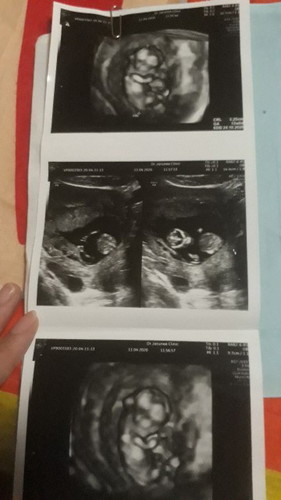

13+วีค

ตั้งครรภ์ได้13+วีคแล้วคะ น้ำหนักไม่ขึ้นเลยเพราะแม่แพ้หนักมาก แต่เด็กสมบูรณ์ แข็งแรงดีคะ